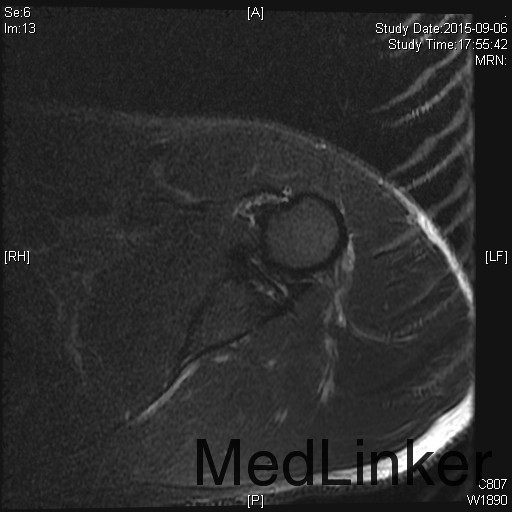

主诉:左肩扭伤后疼痛不适伴弹响10余年,加重3月。 现病史:患者10余年前扭伤左肩关节后出现疼痛不适等症状,伴活动时弹响,以运动时明显。患者当时未重视,未就诊。10余年来患者左肩疼痛不适症状反复发作,曾至外院行局部理疗、小针刀等保守治疗,效果不佳。3月前患者再次扭伤左肩,当即感觉左肩症状加重。来我院就诊,我院行MRI检查示:左肩盂唇信号异常及肱二头肌长头肌腱信号异常。

1、诊断:左肩创伤性前不稳定,左肩SLAP损伤。 2、治疗:全麻下行左肩关节镜下前盂唇、上盂唇修补术。